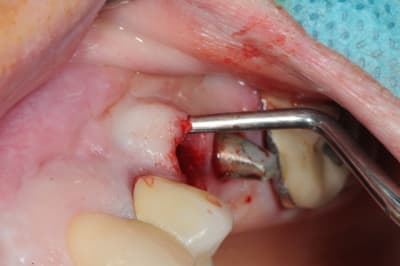

je poursuis donc mon cas clinique si vous voulez bien.

1- curette en appuie sur la face vestibulaire montrant la destruction osseuse.

2- lambeau pleine épaisseur en palatin pour aller chercher un bout de conjonctif qui soit pédiculé.

3 je décole à partit des rebords de la déhiscence osseuse et reste en contacte permanent avec la corticale osseuse tout en décollant la gencive (elle est soulevé donc)

4- comblement avec de la poudre de perlin-pin-pin

( désolé je suis pas au cabinet et je sais plus ce que j'ai mis dedans)

5-6- sutures du conjonctif pour obtenir l'étanchéité (enfin , on essaye)

7- résultat à j+7